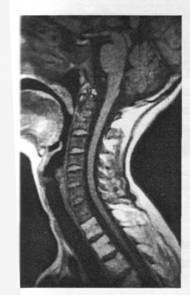

Figura 20. IRM, sectiune sagitala TISE prin coloana cervicala. Modificari mixte de semnal osoase: piesele vertebrale C2- C7 apar infiltrate difuz la un pacient cu mielom multiplu: semnul acestora este marcat hipointens TI. Vertebrele T1-T4 apar cu semnal marcat hiperintens TI, prin reconversie grasoasa post iradiere terapeutica.

• Maduva hipocelulara: apare clasic post-iradiere si este insotita de o conversie grasoasa accentuata cu semnal hiperintens in secventele TI (fig. nr.20);